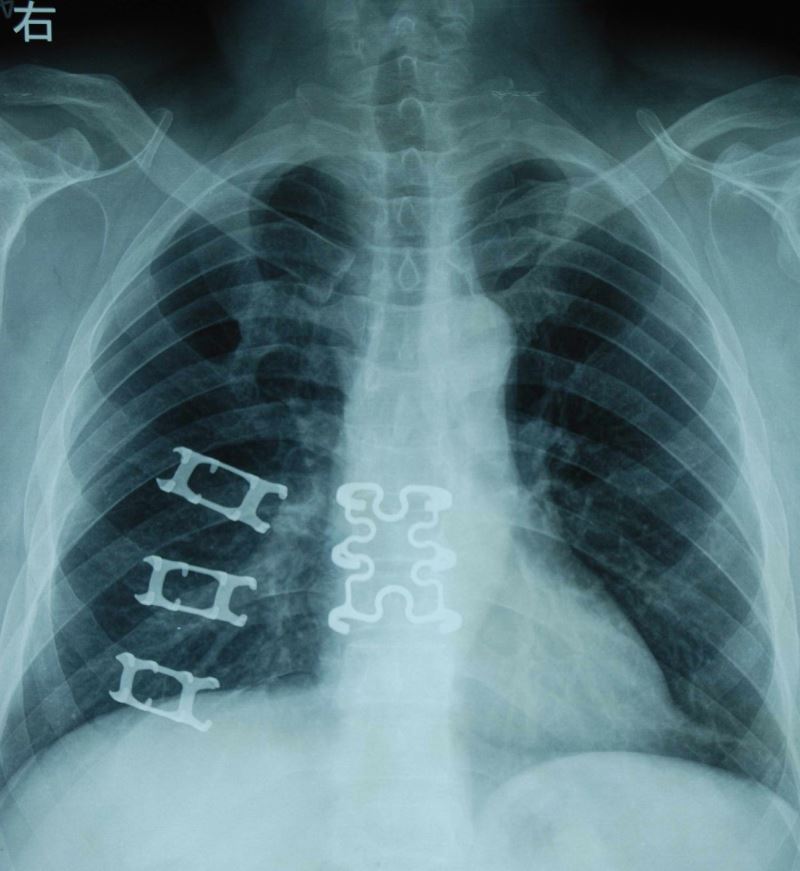

(西脉医疗记忆合金材料肋骨、胸骨X光片1)